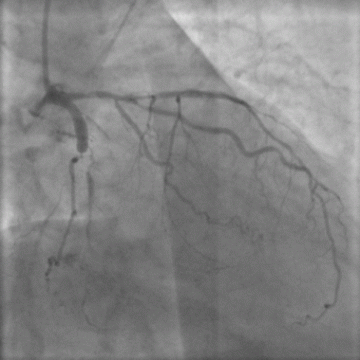

TAXUS药物释放支架在左主干分叉病变的应用

沈阳军区总医院心内科术者:韩雅玲助手:荆全民 栾波病例描述:即往病史:反复发作心前区痛3年,加重10天,高血压30年,无糖尿病。术

导引导管造成左主干夹层一例

大庆市第一医院心脏中心术者:温尚煜病例描述:即往病史:女性,55岁,活动后心前区疼痛1年,加重1月。有吸烟史20余年、高血压10余

TAXUS药物释放支架在左主干全闭塞病变的应用

中山大学附属第一医院心内科术者:杜志民 李怡病例描述:即往病史:患者男性,47岁,因“反复劳累后胸痛6年,加重2天”而入院。既往有

左主干分叉病变的介入治疗

郑州市第七人民医院术者:袁义强助手:刘怀霖 于力 赵育洁病例描述:即往病史:反复发作心前区疼痛2年,加重1天;高血压2年,糖尿病2

CABG术后LM及LAD严重钙化病变的PCI

北京安贞医院术者:陈韵岱助手:宋现涛病例描述:即往病史:患者女性,62岁,因不稳定心绞痛于2004年9月入院。2000年4月行冠脉

T支架技术治疗左主干前三叉病变

第四军医大学西京医院心内科术者:李成祥助手:王海昌 曹丰病例描述:即往病史:心慌胸闷20年余,反复发作心前区痛2天,加重半天,高血

肾移植术后RCA及LAD闭塞病变的PCI

北京安贞医院术者:陈韵岱助手:宋现涛病例描述:即往病史:患者男性,48岁,因“胸闷、夜间阵发性呼吸困难半年”于2004年9月入院。

左主干急性闭塞行急诊介入治疗

北京朝阳医院术者:王红石 徐立 李惟铭病例描述:即往病史:患者,男性,49岁,即往无心脏病史,大量吸烟史30年。此次因突发胸痛1小

左主干分叉病变置入CYPHER SELECT及6个月造影复查-EuroPCR2004转播手术 BJ01

阜外心血管病医院术者:高润霖助手:杨跃进 袁晋青 葛均波(IVUS解说)病例描述:即往病史:65岁,男性。劳力性心绞痛6个月,无心